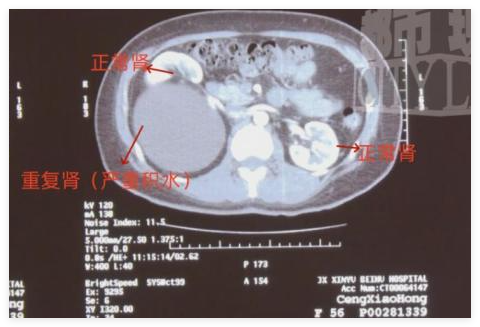

CT 檢查顯示,鄭女士的的體內(nèi)竟然有 " 三個腎 ",醫(yī)學稱之為重復腎。

新余市北湖醫(yī)院泌尿外科 主任 袁劍:右邊的腎有兩個腎,這是一個腎,這下面重度積水的又是一個腎,左邊是個正常的腎。這個積水很大,從上到下幾十層應該有二十幾公分長,這個大小應該是正常腎的三倍。